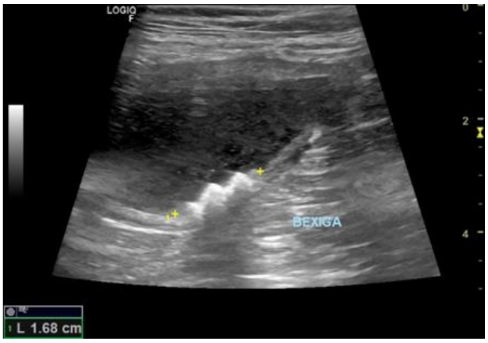

Após detecção de obstrução uretral e múltiplas cistolitíases, foi realizado procedimento de cistocentese para alívio imediato, seguido da implantação de cateter uretral. Com base nos achados da ultrassonografia transoperatória e da uretrocistografia retrógrada, diagnosticou-se ruptura parcial de uretra prostática com presença de cálculo migrado da bexiga para o interior da próstata.

Durante o procedimento cirúrgico, a equipe relata que ao abrir a vesícula urinária esta encontrava-se com paredes bastante espessas, presença de pus em região interna e pontos tendendo à início de necrose. Porém, não foram encontrados todos os cálculos anteriormente visualizados em exames de imagem, apenas um deles, que foi retirado.

Com auxílio da ultrassonografia transoperatória, foi identificado que os cálculos haviam migrado ao interior da lesão prostática, portanto, foi realizado tentativa de hidropulsão através do catéter uretral na tentativa de retorná-los à vesícula urinária, mas sem sucesso com a técnica. O paciente foi então encaminhado para a realização de exame de Uretrocistografia Retrógrada, para confirmar a suspeita levantada de ruptura de uretra em sua porção prostática.

O caso descrito demonstra que a ruptura parcial de uretra prostática em cães, embora rara, deve ser considerada em pacientes com histórico de urolitíase e sinais de obstrução urinária grave. O diagnóstico precoce por meio de exames contrastados e ultrassonografia transoperatória mostrou-se essencial para a definição da conduta terapêutica.